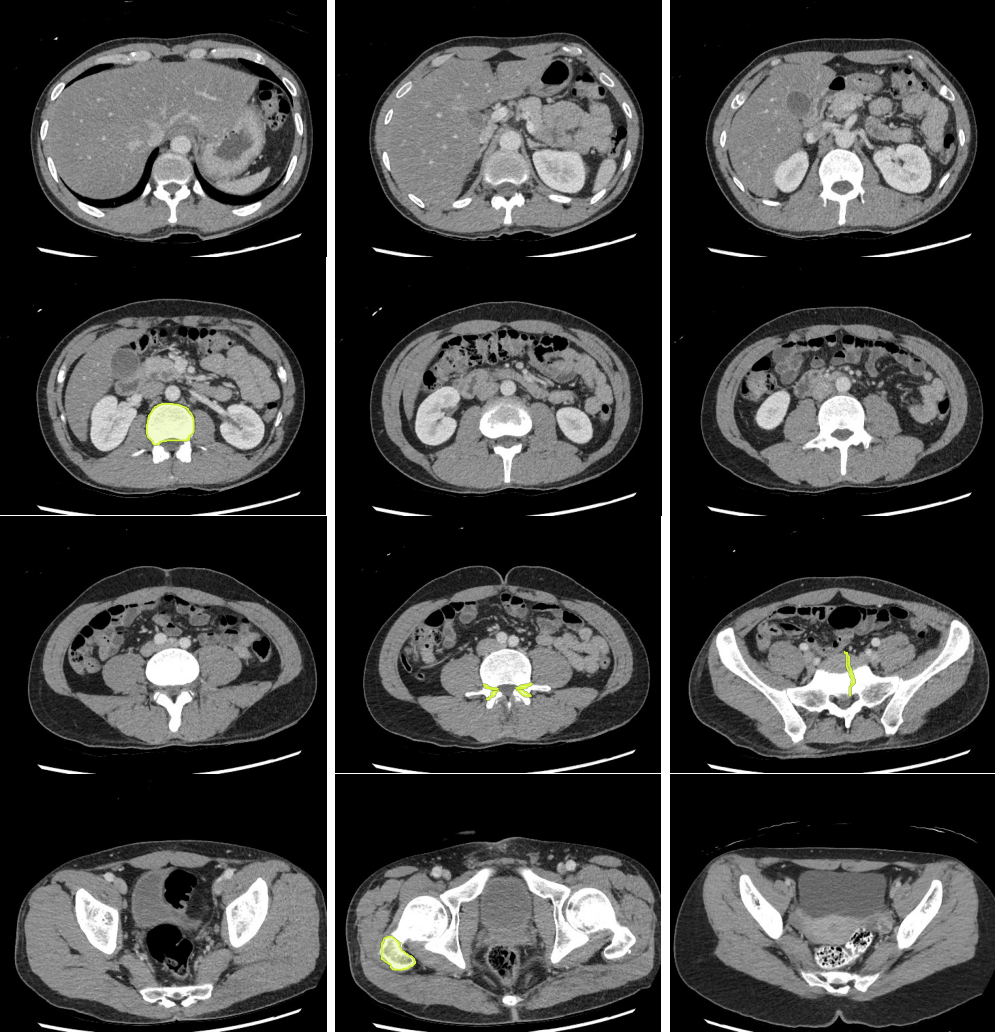

- Masses in the mesentery/peritoneum are often overlooked. Take advantage of multiplanar imaging and look in characteristic locations for peritoneal lesions.

- Kidney masses are also overlooked. Look carefully at the collecting system and for renal contour abnormalities.

- Even without hydronephrosis, consider the possibility of ureteral calculi and attempt to follow the course of the ureters to screen for stones.

- Look carefully for small stones in the ureter/UVJ. Familiarize yourself with the normal location of the ureterovesical junctions and the configuration of the distal ureter to discriminate phleboliths from potential distal ureteral calculi

Slice 1

Slice 2

Slice 3

Slice 4

Slice 5

Slice 6

Slice 7

Slice 8

Slice 9

Slice 10

Slice 11

Slice 12